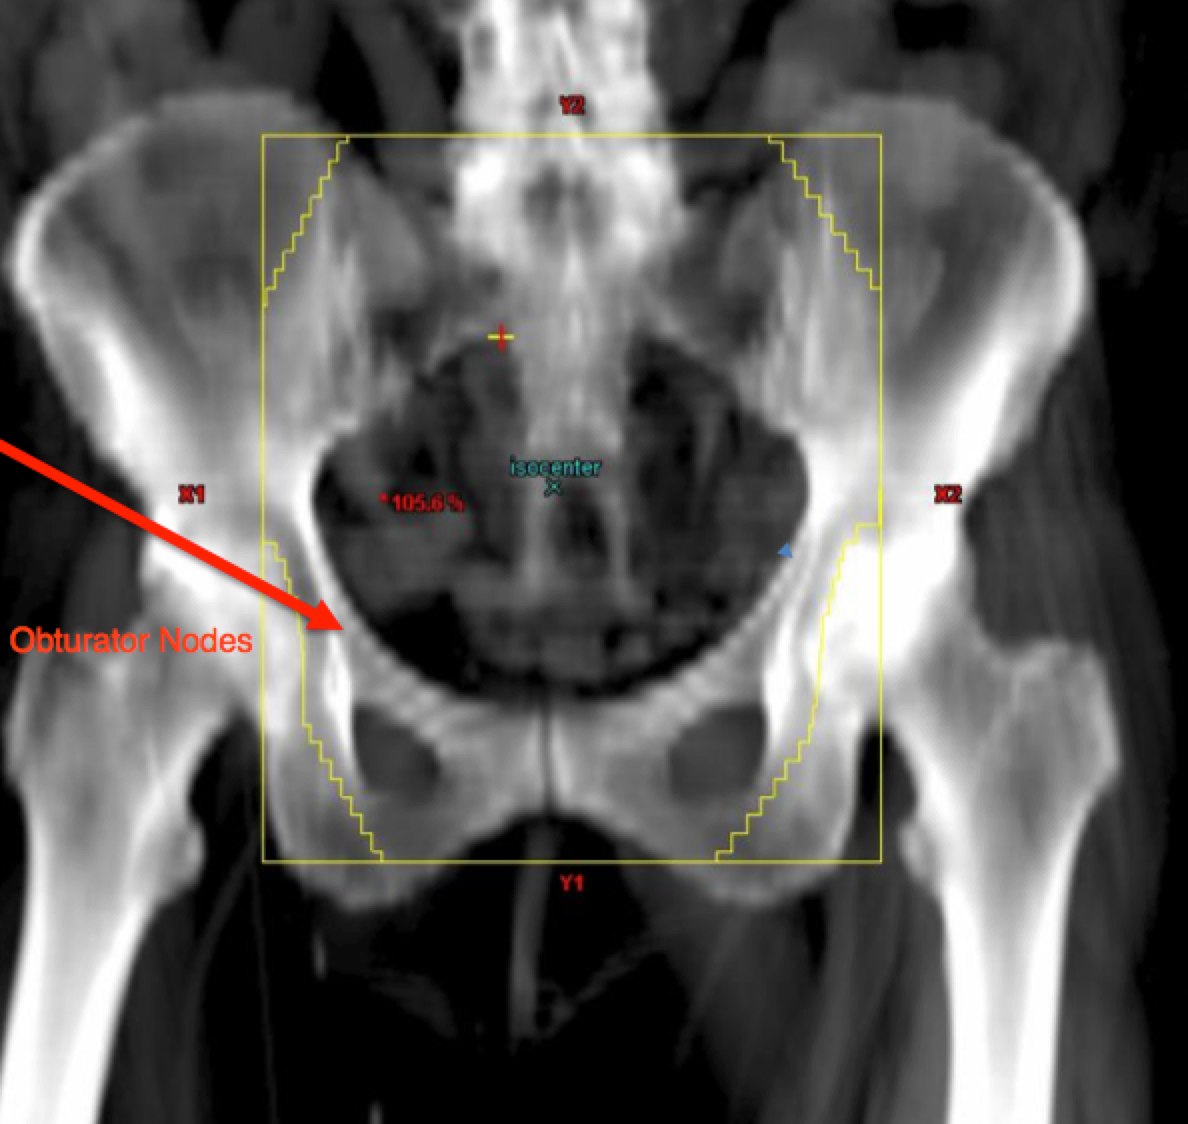

To identify the obturator nodes the following landmarks may be used. (Note: this works for any pelvis where one wishes to find the obturator nodes):

The APPA fields should cover at the superior aspect, the L4/L5 interface or L5/S1 space. The lateral borders are 2 cm lateral to the true pelvis and the inferior borders are at the inferior margin of the obturator foramenae, unless lower is required for vaginal disease extension. This border should be set to 3 cm inferior to the inferior most vaginal disease extent. The femoral heads should be protected.